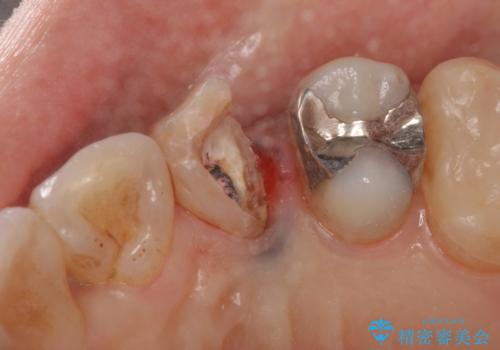

- 左上犬歯の一部が歯ぐきの中まで虫歯になっており、部分矯正をして歯を引っ張り出しました。(エクストリュージョン)

開始前

左:虫歯を除去したところ。遠心が歯ぐきより深い状態です。中:そのままかぶせようとすると、遠心が歯ぐきが腫れやすい状態です。右:エクストリュージョンをしたことで、遠心の歯ぐきの腫れが収まっていることがわかります。